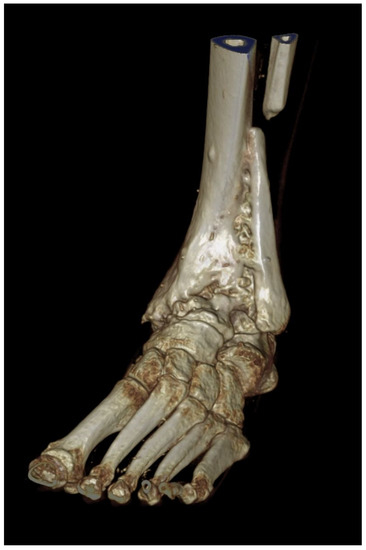

Arthrodesis and Defect Bridging of the Upper Ankle Joint with Allograft Bone Chips and Allograft Cortical Bone Screws (Shark Screw®) after Removal of the Salto-Prosthesis in a Multimorbidity Patient: A Case Report

4. Postoperative Rehabilitation

5. Results